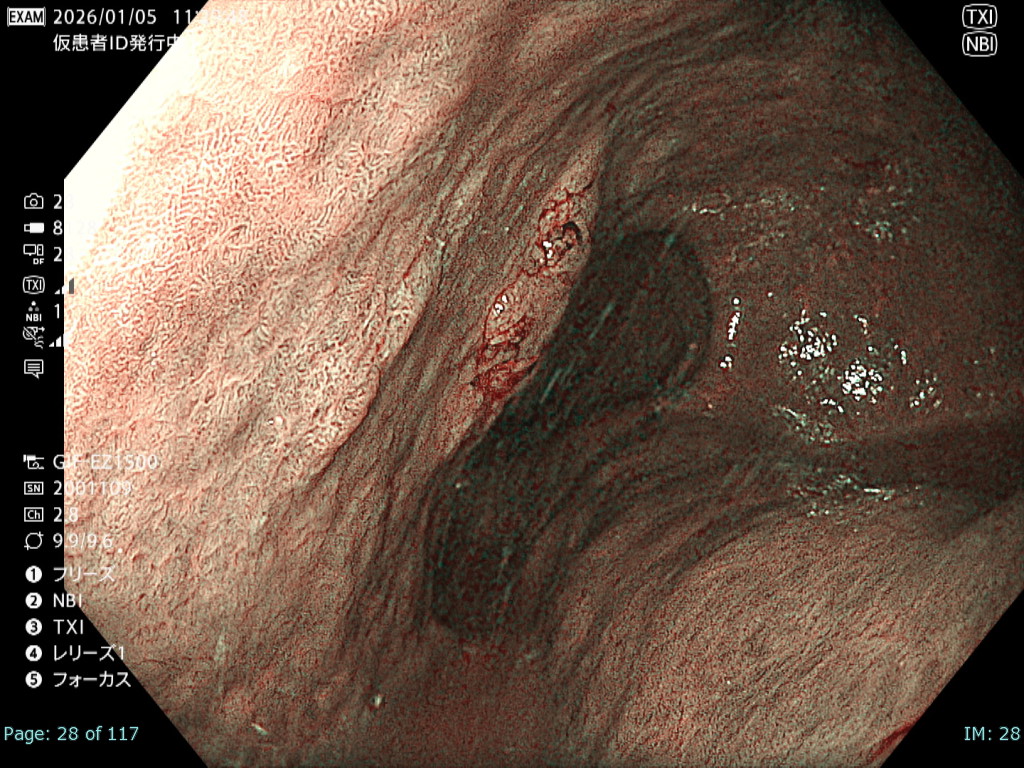

• 白色光観察②(中遠景)

強調設定:A7

図1

白色光非拡大観察では画面全体に良好なフォーカスが得られており、さらにBAI-MAC機能により深部まで十分な明るさが確保されている。そのため、2病変の性状および位置関係を正確に把握することが可能である。